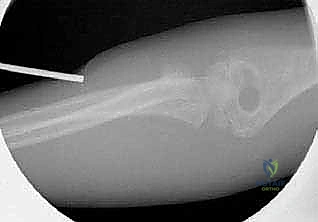

1. الرد المغلق والتثبيت عبر الجلد (CRPP - Closed Reduction and Percutaneous Pinning)

هذه هي التقنية السائدة والمفضلة عالمياً لعلاج كسور عنق الكعبرة لدى الأطفال (تقنية ميتازو Métaizeau Technique). وهي تقنية طفيفة التوغل لا تتطلب شقاً جراحياً كبيراً، مما يحافظ على الأنسجة المحيطة ويقلل من خطر الندبات وتيبس المفصل.